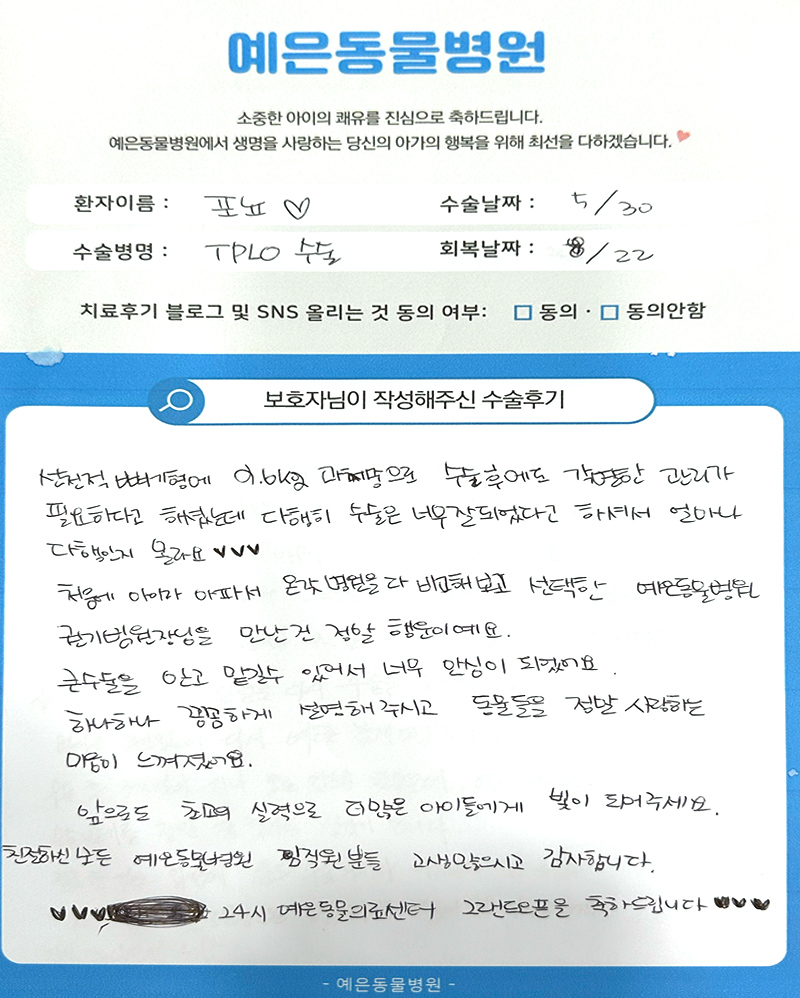

보호자님들이

직접 작성해주신

정형외과 수술 후기 모음

돋보기를 눌러 크게 확인해보세요.

보호자님들이

직접 작성해주신

정형외과 수술 후기 모음

돋보기를 눌러 크게 확인해보세요.